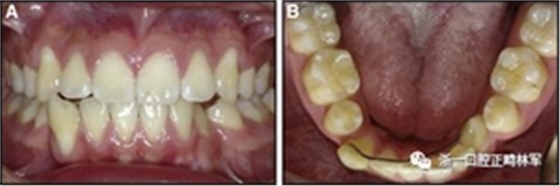

一名28歲的女性(上文提到,其問(wèn)題啟發(fā)了本文)被她的普通牙醫(yī)轉(zhuǎn)診給高級(jí)學(xué)者,因?yàn)樗⒁獾剿南骂M骨固定保持器區(qū)域的牙齒移動(dòng)和牙周損傷。她在15多年前完成了正畸治療,早期放置0.0195英寸固定在所有下頜前牙上的柔性螺旋弓絲保持器。她報(bào)告說(shuō),她在治療后的第一年經(jīng)常拜訪她的正畸醫(yī)生,但從此以后就沒(méi)有見(jiàn)過(guò)他。

臨床檢查顯示固定保持器完好,弓絲沒(méi)有斷裂(圖13)。在下頜右側(cè)中切牙唇側(cè)和鄰近側(cè)切牙的舌側(cè)注意到有牙齦退縮。這些牙齒在退縮方向上存在顯著的扭矩差異。下頜的左側(cè)尖牙頰側(cè)錯(cuò)位,而右側(cè)尖牙舌側(cè)傾斜。三維射線照片證實(shí)了下頜右側(cè)尖牙面?zhèn)妊啦酃菃适?,右?cè)中切牙的喪失程度較輕。右側(cè)側(cè)切牙根也從舌側(cè)骨面上扭轉(zhuǎn)出來(lái)(圖14)。

圖13.粘合到尖牙和切牙上的柔性螺旋弓絲保持器,伴有牙齦退縮和附著喪失,中切牙之間嚴(yán)重的扭矩差異以及兩顆尖牙的橫向移動(dòng)和扭矩。牙周問(wèn)題和牙齒移動(dòng)的嚴(yán)重程度均為牙周正畸聯(lián)合治療的指征:A,正面視圖; B,咬合面視圖。